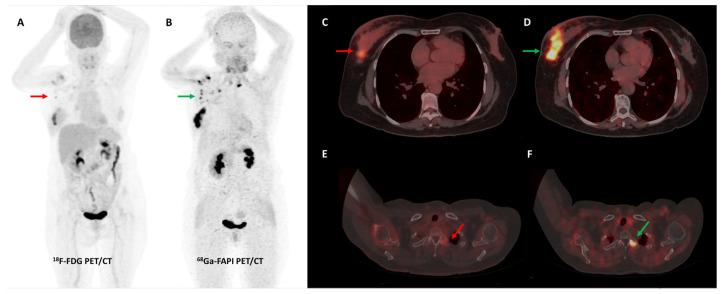

Despite revolutionizing the field of oncological imaging, Positron Emission Tomography (PET) with [F]Fluorodeoxyglucose (FDG) as its workhorse is limited by a lack of specificity and low sensitivity in certain tumor subtypes. Fibroblast activation protein (FAP), a type II transmembrane glycoprotein, is expressed by cancer-associated fibroblasts (CAFs) that form a major component of the tumor stroma. FAP holds the promise to be a pan-cancer target, owing to its selective over-expression in a vast majority of neoplasms, particularly epithelial cancers. Several radiolabeled FAP inhibitors (FAPI) have been developed for molecular imaging and potential theranostic applications. Preliminary data on FAPI PET/CT remains encouraging, with extensive multi-disciplinary clinical research currently underway. This review summarizes the existing literature on FAPI PET/CT imaging with an emphasis on diagnostic applications, comparison with FDG, pitfalls, and future directions.

尽管正电子发射断层扫描(PET)以[F]氟脱氧葡萄糖(FDG)作为其主要显像剂,彻底改变了肿瘤影像学领域,但在某些肿瘤亚型中,它存在特异性不足和灵敏度较低的局限性。成纤维细胞活化蛋白(FAP)是一种II型跨膜糖蛋白,由构成肿瘤基质主要成分的癌症相关成纤维细胞(CAF)表达。由于FAP在绝大多数肿瘤,尤其是上皮癌中选择性过度表达,它有望成为一种泛癌靶点。已经开发了几种放射性标记的FAP抑制剂(FAPI)用于分子成像和潜在的诊疗应用。FAPI PET/CT的初步数据仍然令人鼓舞,目前正在进行广泛的多学科临床研究。这篇综述总结了关于FAPI PET/CT成像的现有文献,重点是诊断应用、与FDG的比较、陷阱和未来方向。